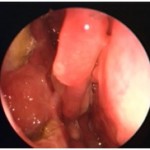

| Figure 1a and 1b. Persistent sinusitis despite widely open sinus cavities | |

Figures 4a and 4b Pre- and Post-Rhinotopic Therapy: Chronic hyperplastic sinusitis in a patient prior to the topical treatment (left). The ethmoid and frontal mucosa is polypoid; the maxillary antrostomy is patent. Same patient after completion of the rhinotopic protocol (right). The sinus mucosa health has been restored.